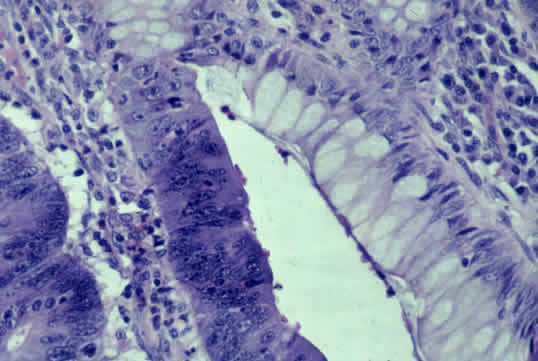

在结肠腺瘤腺体内出现的腺癌:注意恶性细胞非常暗的染色,以及细胞内各级细胞核的存在。比较腺瘤细胞(腺体顶部)和癌细胞(腺体底部)(图片由以下人员提供:C.Whitaker Sewell,医学博士-埃默里大学医学院病理学教授)。